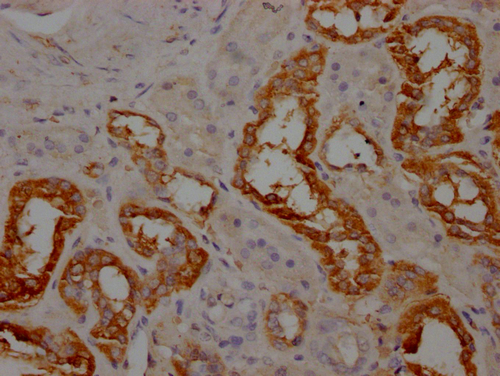

IHC image of CSB-PA001947LA01HU diluted at 1:100 and staining in paraffin-embedded human kidney tissue performed on a Leica BondTM system. After dewaxing and hydration, antigen retrieval was mediated by high pressure in a citrate buffer (pH 6.0). Section was blocked with 10% normal goat serum 30min at RT. Then primary antibody (1% BSA) was incubated at 4°C overnight. The primary is detected by a Goat anti-rabbit IgG labeled by HRP and visualized using 0.05% DAB.